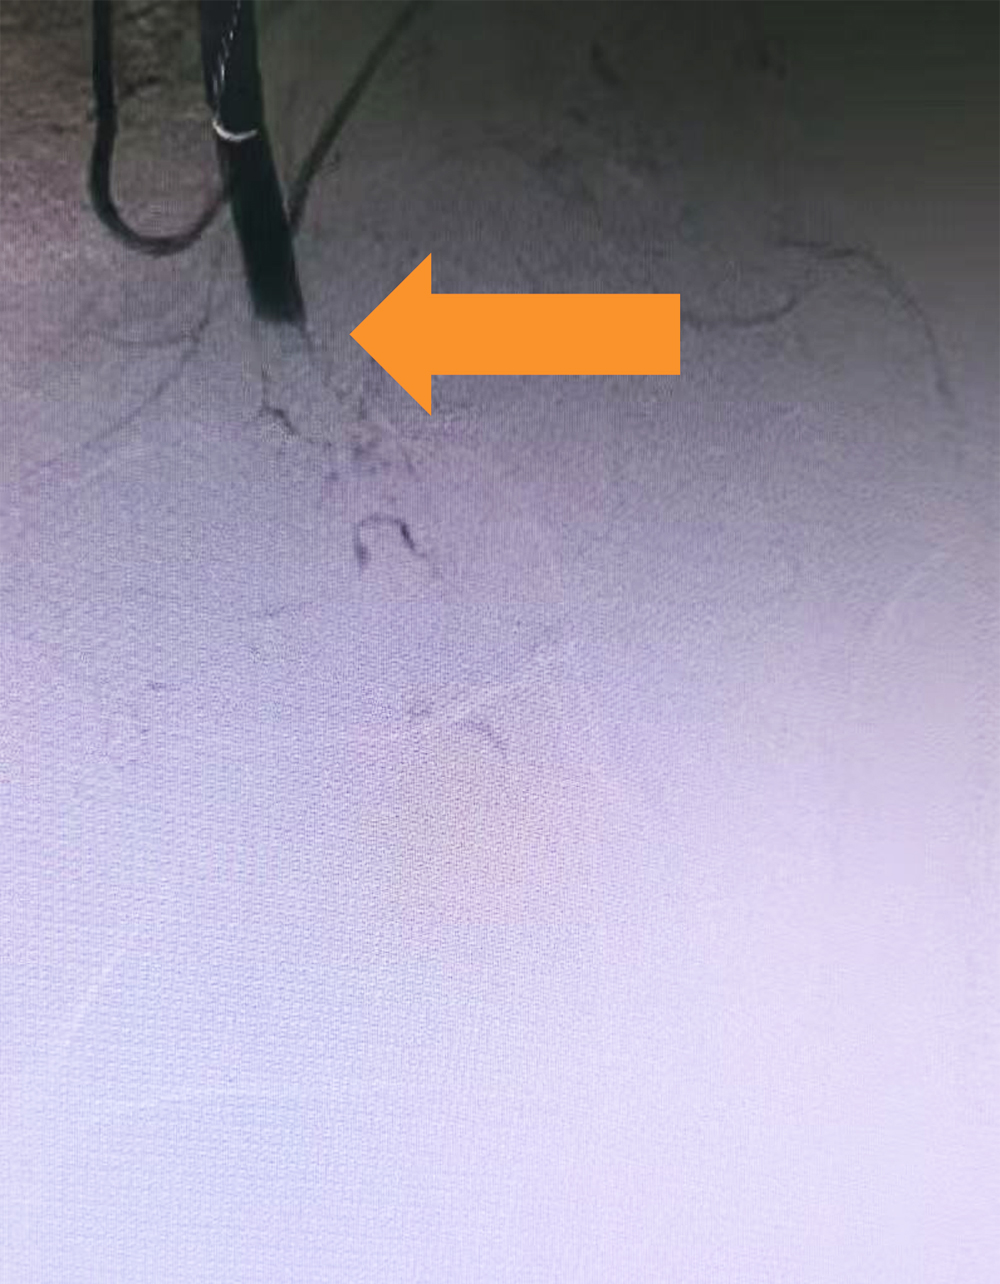

取栓前 左下肢动脉造影,显示股动脉栓塞,远端无血流